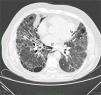

Chest computed tomography showing a thin curved line of gas surrounding the bronchovascular bundles of the right lower lobe, associated with interstitial emphysema (black arrows); extensive emphysematous changes were also observed in the mediastinum close to the heart and descending thoracic artery (pneumomediastinum: white arrows).

Interstitial emphysema (IE) is an uncommon lung disease associated with barotrauma, and is seen almost exclusively in neonates with respiratory distress syndrome. It is caused by the invasion of gas into the pulmonary interstitial space surrounding the bronchovascular bundles due to sudden changes in lung volumes and transpulmonary pressure. Secondary changes in the alveolar sacs cause the alveolar septa to rupture.1 The difference in pressure, always greater in the alveolar compartment than in the mediastinum, increases the flow of gas bubbles to the mediastinal compartment, producing pneumomediastinum. The effect of gravity causes the bubbles to rise to the neck, producing subcutaneous emphysema. We report the case of a 65-year-old man, former smoker (30 pack-years), with upper lobar emphysema and lower lobar fibrosis (combination of pulmonary fibrosis and emphysema [CPFE]). He presented in the hospital with worsening dyspnea at rest. On admission, he had intense tachypnea (32 breaths per minute) due to severe hypoxemia (38.5mmHg) and a heart rate of 90 beats per minute. Images from a high resolution computed tomography (HCRT) scan of the chest performed 1 year previously (not attached) showed significant involvement of the lung architecture with patterns of emphysema and concomitant fibrosis. Clinical diagnostic procedures were completed with full lung function tests (LFT) and spirometry. Approximately 4hours after spirometry, another chest HRCT was performed to compare the resulting morphological functional data with the previous examination. Unexpectedly, the repeat HRCT showed a significant amount of air in the mediastinal compartment (pneumomediastinum), and small gas bubbles were seen in the pulmonary interstitial space surrounding the bronchovascular bundles, attributed, in the absence of pneumothorax, to IE (Fig. 1). The patient had no signs of worsening chest pain or dyspnea after the HRCT or in the following hours. After 10 days of complete bed rest, another HRCT was performed, showing almost complete reabsorption of the air in the mediastinum and surrounding the bronchovascular bundles.